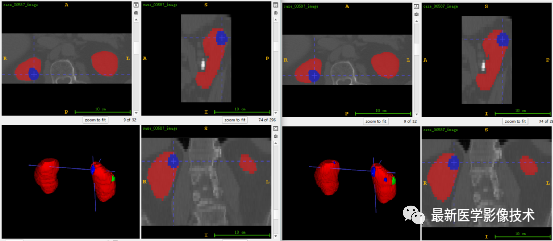

肾脏粗分割

1、首先采用人体分割方法提取人体区域,然后根据人体ROI从原始图像和mask提取ROI区域。

2、分析ROI图像,得到图像平均大小是104x377x511,因此将图像缩放到固定大小240x256x256。图像预处理,对步骤1的ROI图像进行(-200,400)窗宽窗位截断,然后采用均值为0,方差为1的方式进行归一化处理,再将数据分成训练集和验证集,对训练集进行2倍数据增强。

3、搭建VNet3d网络,使用AdamW优化器,学习率是0.001,batchsize是1,epoch是150,损失函数采用二值化的dice和交叉熵。

4、训练结果和验证结果